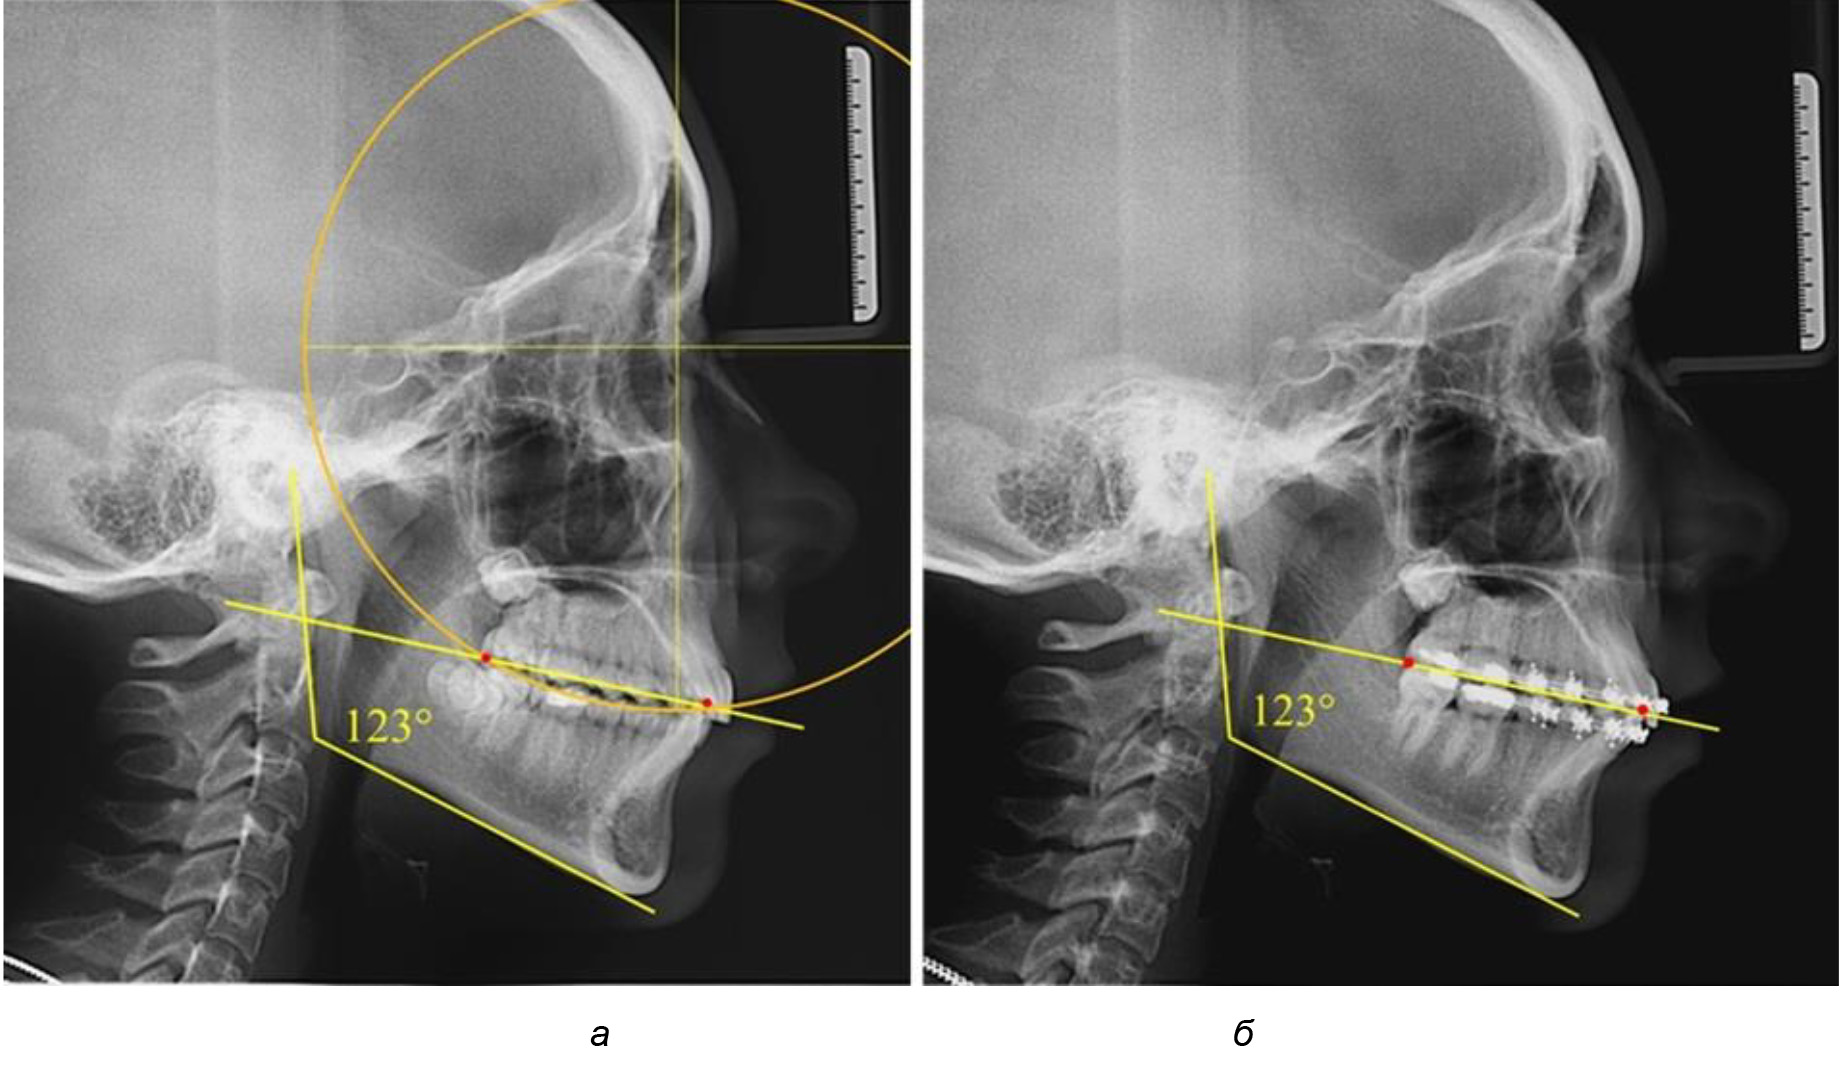

Рис. 2. Особенности кривой Spee на ТРГ (а) и ОПТГ (б) у людей с признаками вертикального роста

На рентгенограммах людей 2-й подгруппы (30 человек с нейтральным типом роста) величина угла нижней челюсти в среднем составила (120,34 ± 2,19) ° и характеризовала нейтральный тип нижней челюсти.

Глубина кривой Spee в среднем по 2-й подгруппе составил (3,54 ± 0,58) мм, что было незначительно меньше, чем при анализе аналогичного показателя 1-й подгруппы.

Достоверных различий с показателями, полученными при анализе ТРГ и ОПТГ, нами не отмечено (р ˃ 0,05). Деление величины радиуса круга к длине окклюзионной линии составило 1,612 ± 0,02, что, так же как и в 1-й подгруппе, было близким по значению к числу Фибоначчи (1, 618).